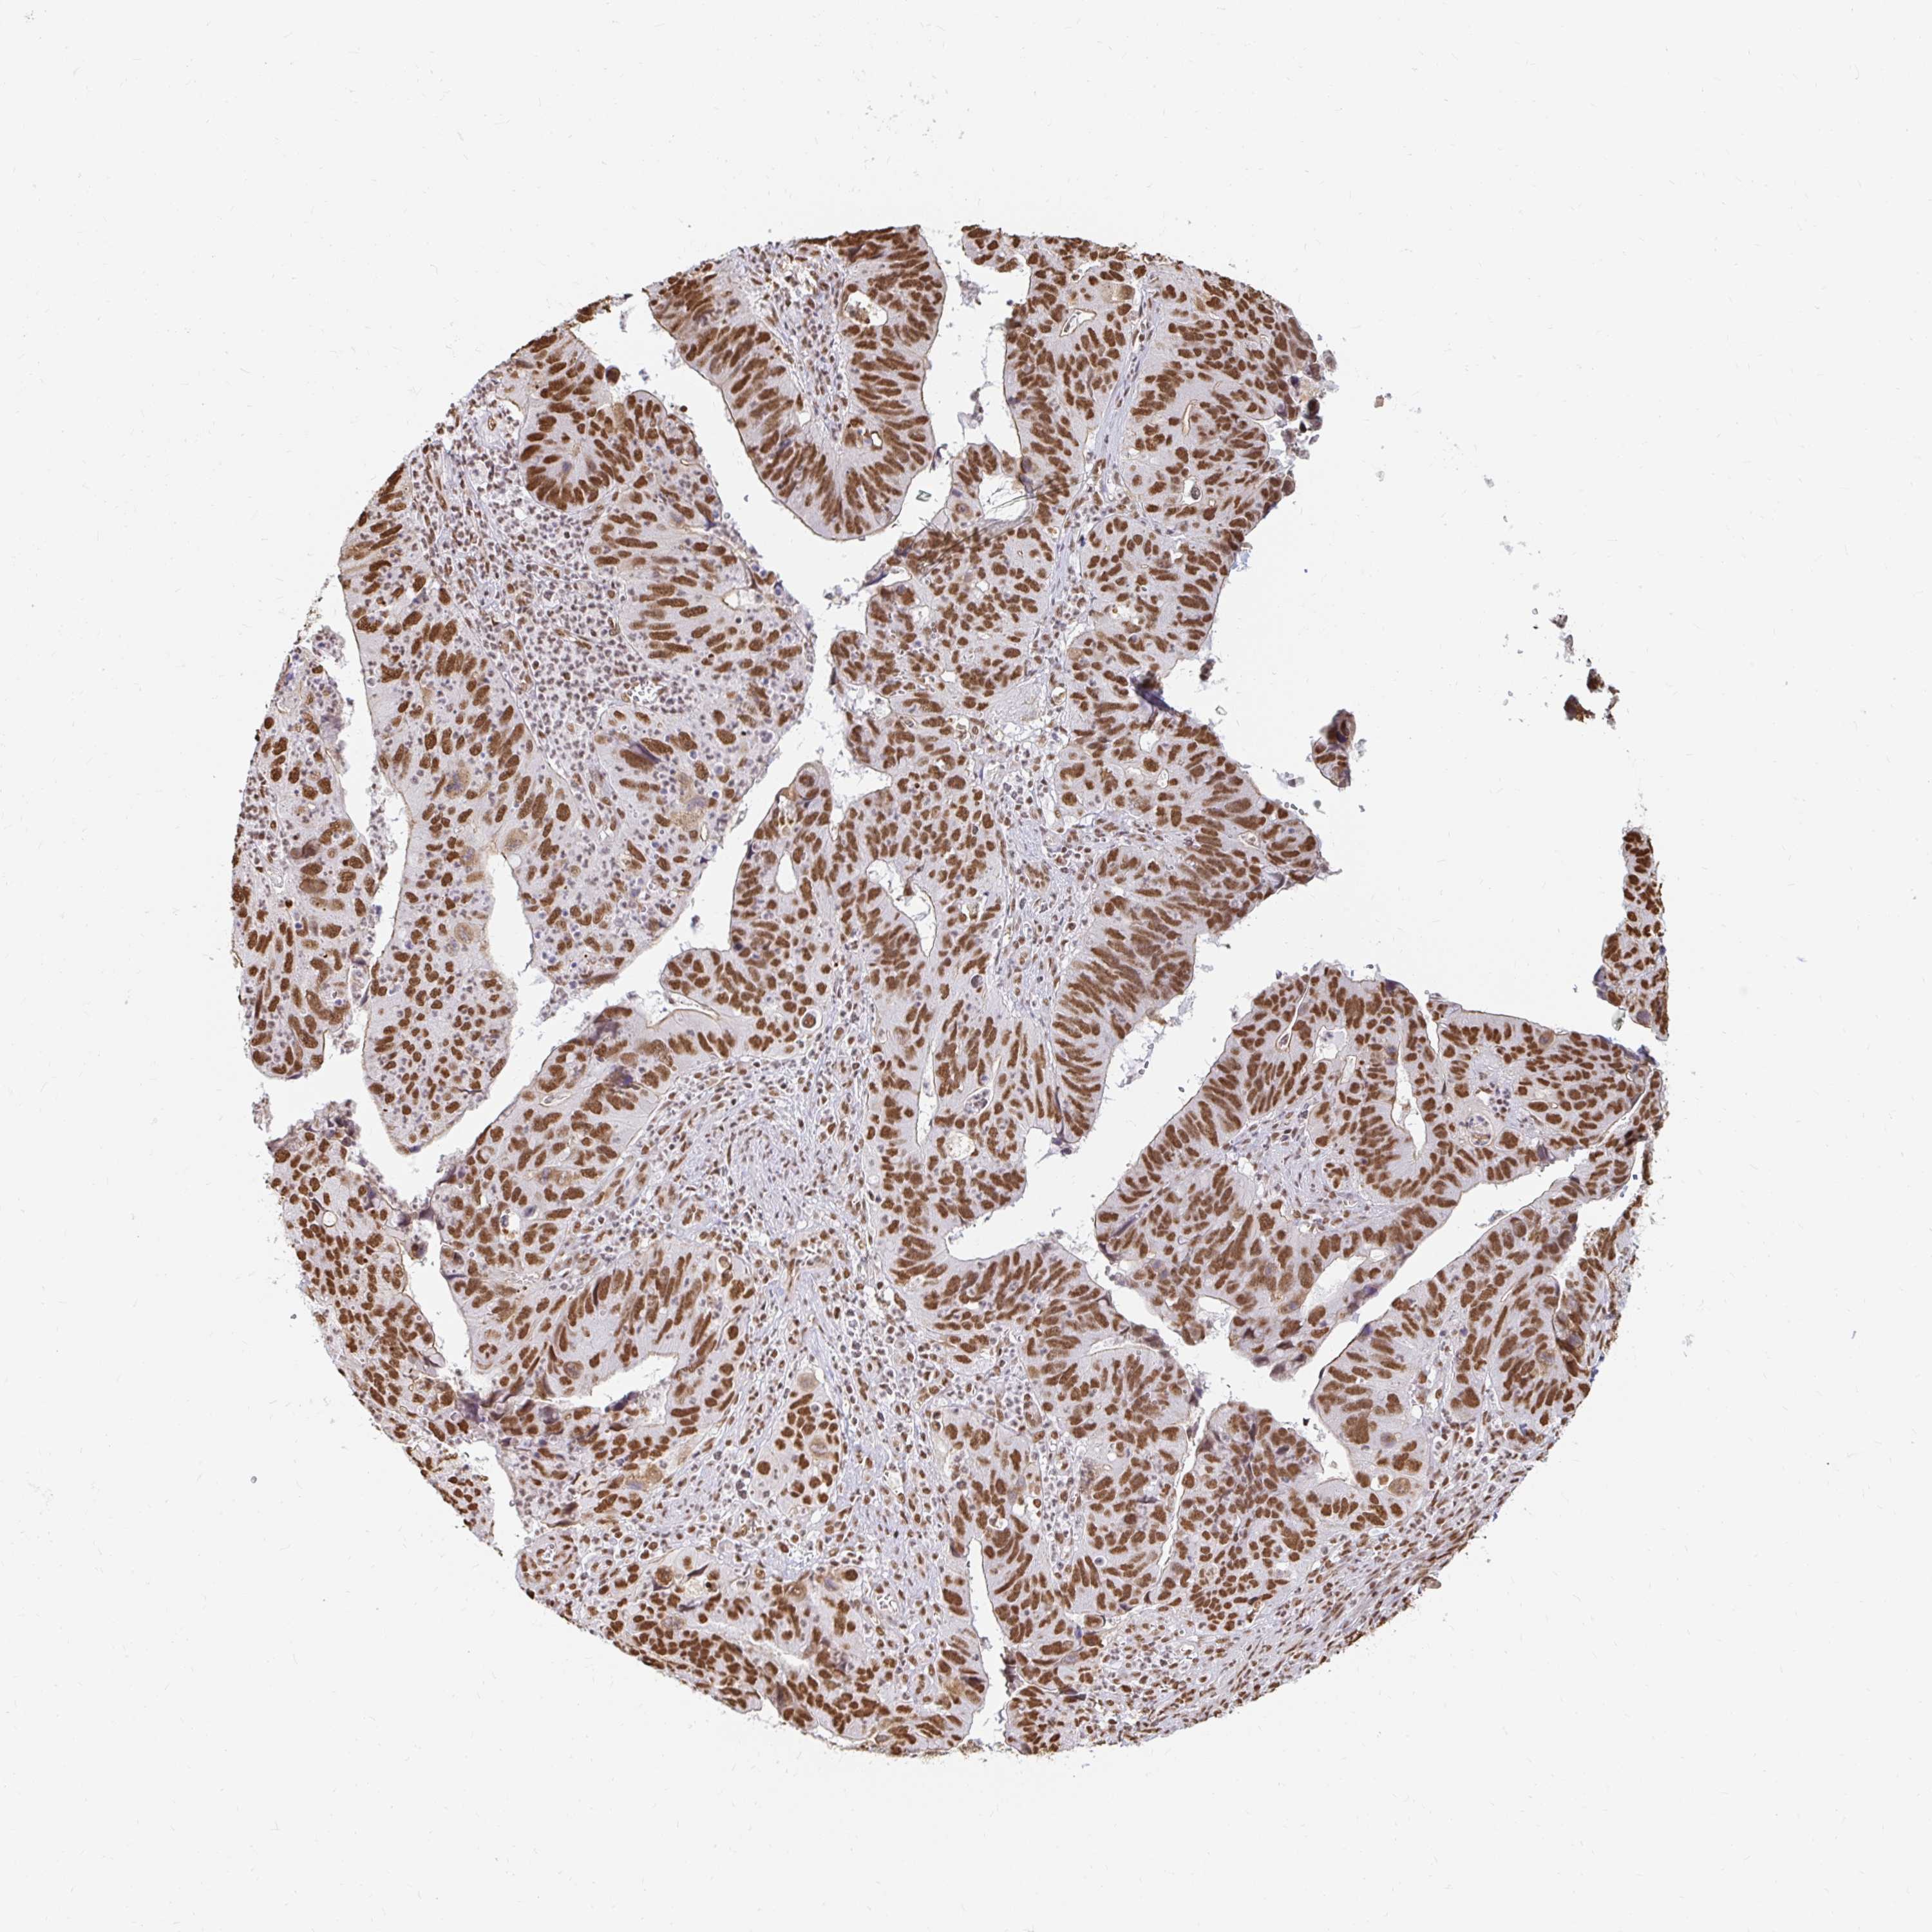

STOMACH CANCER - Protein expressioni

A mouse-over function shows sample information and annotation data. Click on an image to view it in a full screen mode. Samples can be filtered based on level of antibody staining by selecting one or several of the following categories: high, medium, low and not detected. The assay and annotation is described here.

Note that samples used for immunohistochemistry by the Human Protein Atlas do not correspond to samples in the TCGA dataset.

Antibody stainingi

Antibody staining in the annotated cell types in the current human tissue is reported as not detected, low, medium, or high, based on conventional immunohistochemistry profiling in selected tissues. This score is based on the combination of the staining intensity and fraction of stained cells.

Each image is clickable and will lead to virtual microscopy that enables deeper exploration of all samples and also displays staining intensity scores, fraction scores and subcellular localization as well as patient and tissue information for each sample.

Antibody HPA041057

Antibody HPA058707

Antibody CAB011532

Staining

High

Medium

Low

Not detected

Intensity

Strong

Moderate

Weak

Negative

Quantity

>75%

75%-25%

<25%

None

Location

Nuclear

Cytoplasmic/membranous

Cytoplasmic/membranous,nuclear

Adenocarcinoma, NOS

Adenocarcinoma, High grade